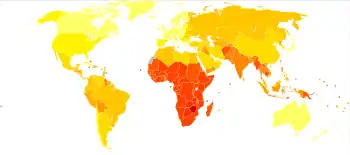

Epidemiology

- no data

- ≤250

- 250–500

- 500–1000

- 1000–2000

- 2000–3000

- 3000–4000

- 4000–5000

- 5000–6250

- 6250–12,500

- 12,500–25,000

- 25,000–50,000

- ≥50,000

In 2010, about 10 million people died of infectious diseases.[84]

The World Health Organization collects information on global deaths by International Classification of Disease (ICD) code categories. The following table lists the top infectious disease by number of deaths in 2002. 1993 data is included for comparison.

The top three single agent/disease killers are HIV/AIDS, TB and malaria. While the number of deaths due to nearly every disease have decreased, deaths due to HIV/AIDS have increased fourfold. Childhood diseases include pertussis, poliomyelitis, diphtheria, measles and tetanus. Children also make up a large percentage of lower respiratory and diarrheal deaths. In 2012, approximately 3.1 million people have died due to lower respiratory infections, making it the number 4 leading cause of death in the world.[90]